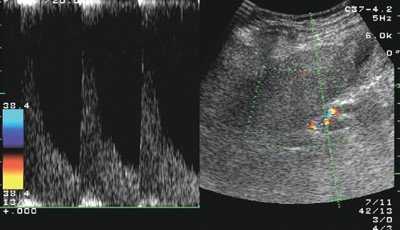

У больных циррозом печени, воздерживавшихся от употребления алкоголя, отмечалась тенденция к нормализации уровня печеночных ферментов: активность алкогольного гепатита была невысокой. Увеличение размеров правой доли печени было выражено в меньшей степени. ИР печеночной артерии превышал 0,7, что характерно для цирроза печени любой другой этиологии (рис. 1). Размеры селезенки, диаметр воротной вены и скорость воротного кровотока были такими же в контрольной группе. У больных в группе 3 различия с контрольной группой отсутствовали: сохранялись лабораторные признаки активного алкогольного гепатита (высокий уровень ГГТ, преобладание ACT над АЛТ), гепатомегалия и не характерно низкий для цирроза печени ИР печеночной артерии (0,59±0,05) (рис. 2).

Рис. 1. Эхограмма: спектр кровотока в печеночной артерии у больного циррозом печени с неактивным алкогольным гепатитом (ИР=0,75).